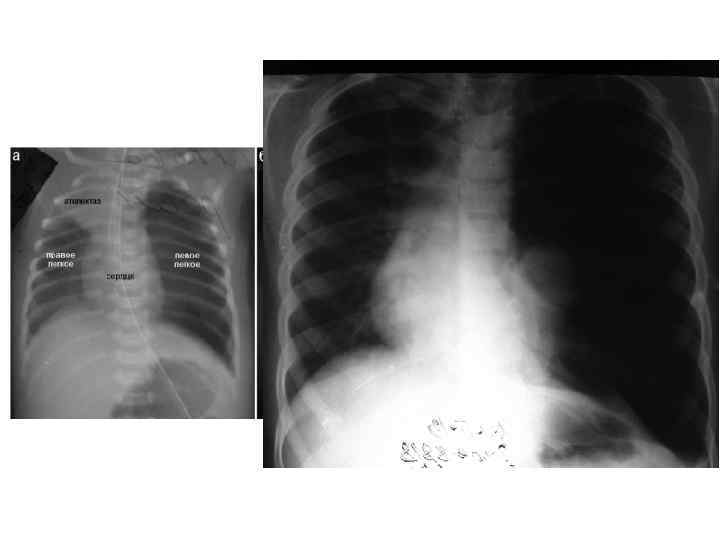

• Грудная клетка имеет форму усеченного конуса. Большой диаметр нижней грудной клетки обусловлен высоким расположением органов брюшной полости, особенно печени. После первого вдоха легкие расправляются, верхняя часть грудной клетки несколько расширяется, верхние ребра принимают почти горизонтальное положение. • The thorax has the shape of a truncated cone. The large diameter of the lower rib cage due to the high location of the abdominal organs, especially the liver. After the first breath the lungs are straightened, the upper part of the chest somewhat expands the upper ribs take a nearly horizontal position.

Дыхательная система Respiratory system • Нос короткий, нижний носовой ход недоразвит, а остальные — узкие. Слизистая оболочка полости носа тонкая, обильно снабжена кровеносными сосудами, склонна к отеку. • Легкие новорожденного богаты кровеносными сосудами, межуточной тканью и бедны эластической тканью. Лимфатические щели и капилляры широкие. Вследствие этих особенностей легкие более полнокровны, менее воздушны и эластичны, что создает условия для возникновения застойных явлений и развития инфекции. • The nose is short, the lower nasal passage underdeveloped, and the rest narrow. The mucous membrane of the nasal cavity is thin, richly supplied with blood vessels, prone to edema. • Lungs of a newborn is rich in blood vessels, interstitial tissue and is poor in elastic tissue. Lymphatic capillaries and cracks wide. Due to these features light a fuller, less airy and stretchy, which creates conditions for the emergence of stagnation and the development of infection.

• У новорожденных дыхание частое и поверхностной, характерны аритмия и лабильность дыхания. Число дыхательных движений у доношенного новорожденного от 40 до 50— 60 в 1 мин. • Становление функции дыхания у новорожденных происходит при участии легочного сурфактанта (антиателектатического фактора). При недостатке сурфактанта (например, при гипоксии) развивается синдром дыхательных расстройств (СДР). • Newborns breathing is frequent and superficial, characterized by lability and arrhythmias breathing. The number of respiratory movements in full-term newborn from 40 to 50 -60 in 1 min. • The formation of the respiratory function in newborns occurs when the pulmonary surfactant (antiateroskleroticescoe factor). With a lack of surfactant (e. g. , during hypoxia) develops respiratory distress syndrome (SDR).